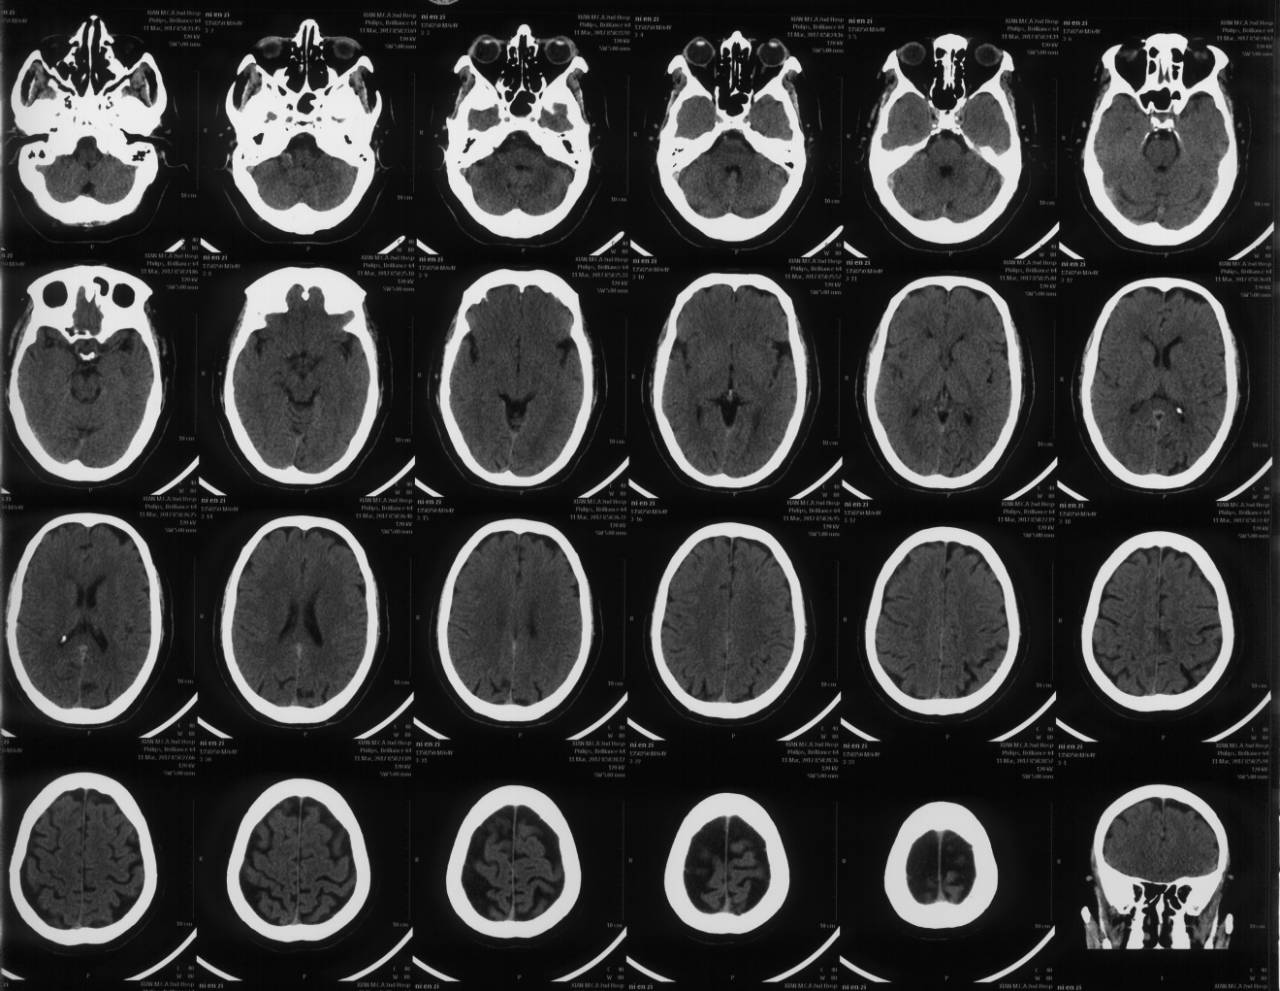

完善相关检查后,急诊行全脑血管造影术

示右侧大脑后动脉P1段不显影,右侧后交通动脉开放。左侧P1中段闭塞,左侧前循环无明显代偿。考虑该血管为责任血管,急诊行血管开通术。

术后即刻CT

术后12小时头CT,病人目前语言功能改善,右半身肌力3级以上

术后48小时头CT